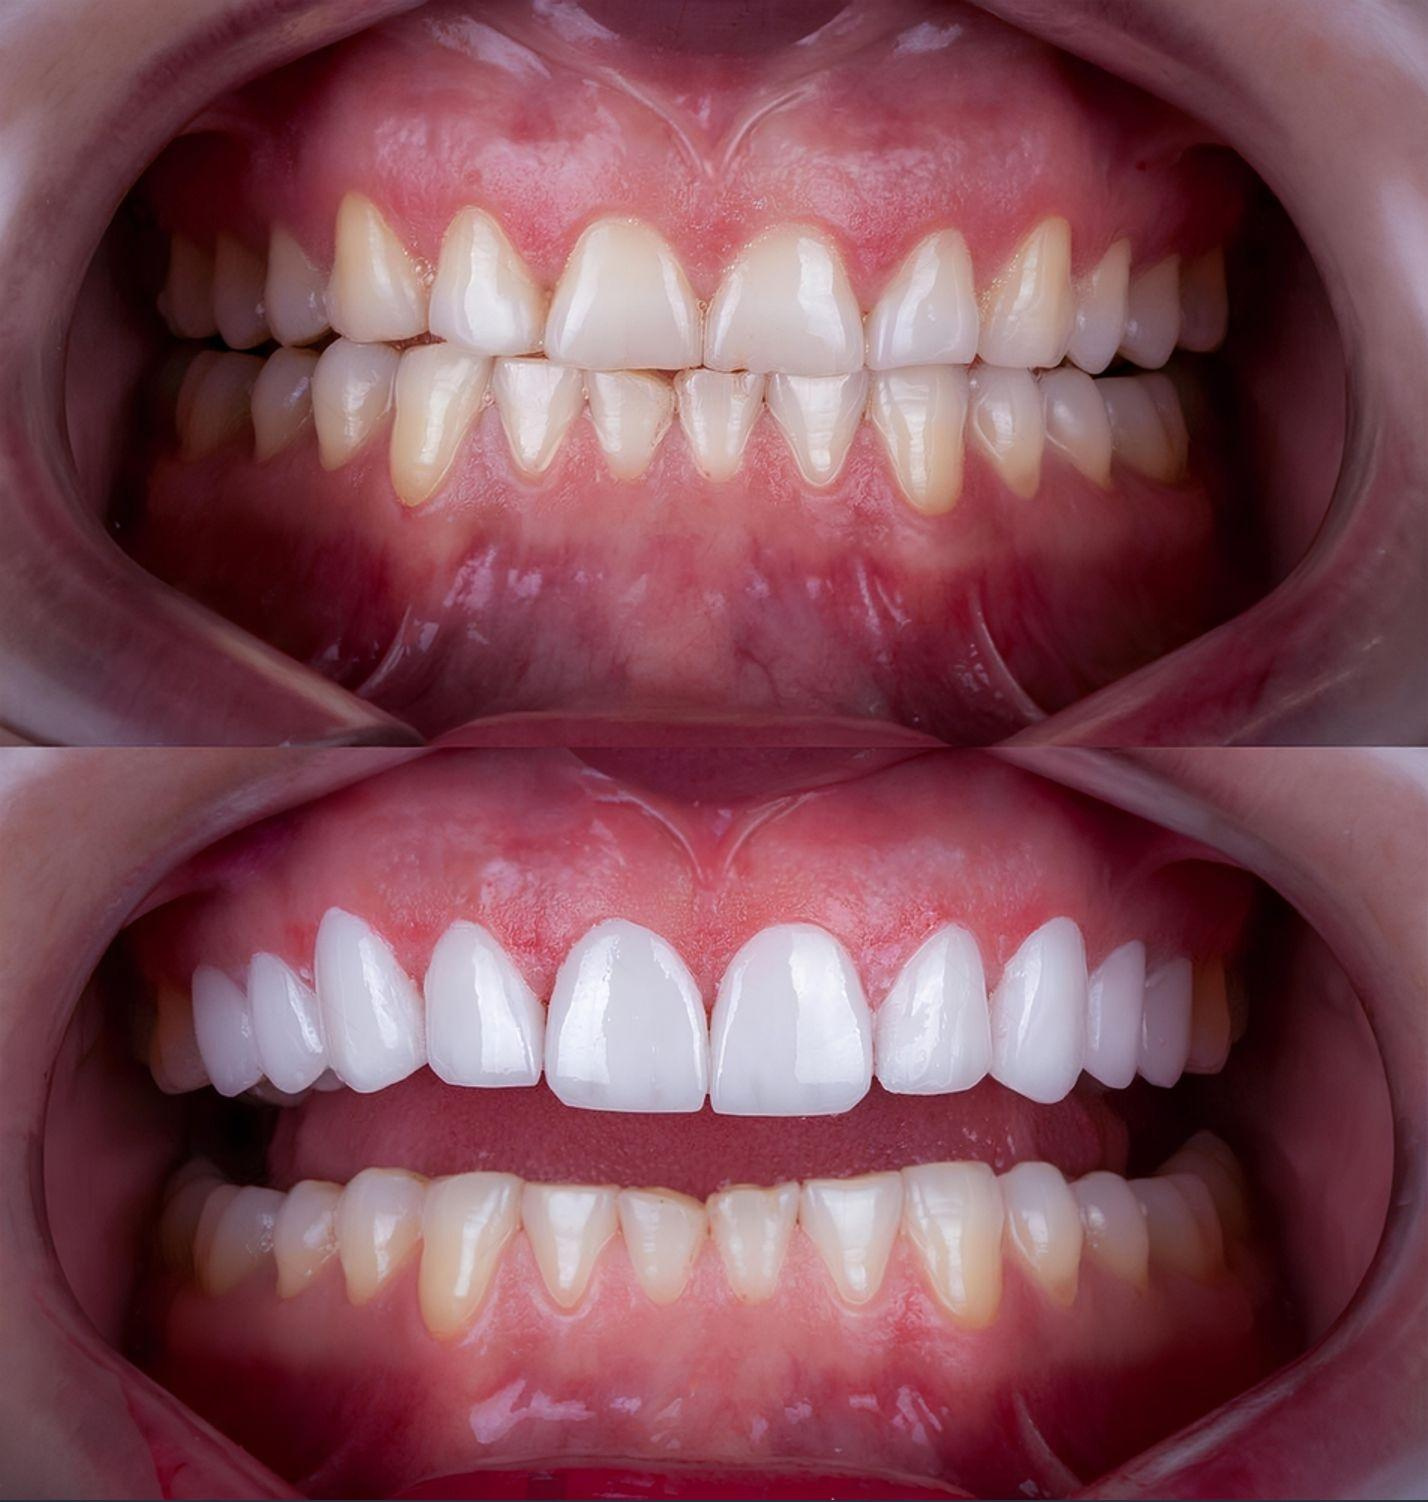

From subtle refinements to dramatic changes, these before-and-after cases highlight the power of expert care and advanced dental technology.

Smile Transformations